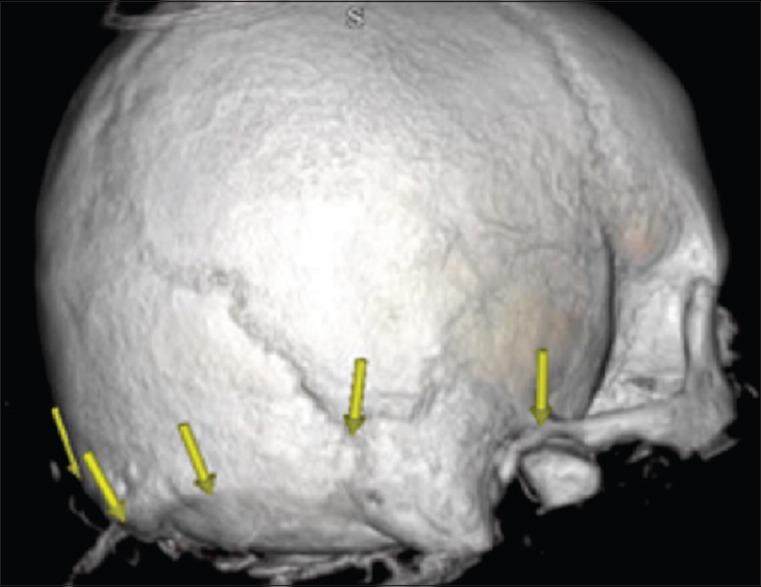

Several cadaveric studies demonstrate reliable localization of the transverse sinus and the transverse sigmoid junction (TSJ). These studies use the line drawn from the inion to the posterior root of the zygoma (IZ) and the asterion, respectively. We investigated how the size difference between the right and left transverse sinuses (TS) and sigmoid sinuses (SS) affected the accuracy of their respective superficial landmarks, particularly with regards to where this relationship may result in unsafe and/or complicated surgical access.

We utilized Vitrea software to render three-dimensional images based on computed tomographic angiography (CTA). We measured the relationship between the TS and SS to their respective superficial landmarks.

We analyzed 50 patients in this study. The distal TS was found caudal to the inion-to-zygoma (IZ) line on average by 5.0 ± 4.3 mm on the right and 6.4 ± 9.3 mm on the left. The mid TS was found cranial on average 3.5 ± 5.7 mm on the right and 3.2 ± 6.0 mm cranial on the left to the superior nuchal line (SNL). The distance from the asterion to the SS was 11.5 ± 2.4 mm medial on the right and 12.1 ± 4.4 mm medial on the left. The average distance was greater on the left than the right when using the IZ landmark. This was directly proportional to the size difference of the sinuses ( = 0.15, = 0.03).

Statistically significant differences between the right and left TS and SS were seen in terms of size. This appeared to correlate nicely to the differences observed between the locations of the TSs' and their respective superficial landmarks.

多项尸体研究表明,横窦和横乙状窦交界处(TSJ)的定位可靠。这些研究分别使用从枕外隆凸至颧骨后根(IZ)的连线和星点。我们研究了左右横窦(TS)和乙状窦(SS)之间的大小差异如何影响其各自表面标志的准确性,特别是这种关系可能导致不安全和/或复杂手术入路的情况。

我们利用Vitrea软件根据计算机断层血管造影(CTA)生成三维图像。我们测量了TS和SS与其各自表面标志之间的关系。

我们在本研究中分析了50例患者。发现右侧远端TS平均位于枕外隆凸至颧骨连线(IZ)下方5.0±4.3mm处,左侧为6.4±9.3mm。右侧TS中部平均位于上项线(SNL)上方3.5±5.7mm处,左侧为3.2±6.0mm。从星点到SS的距离右侧内侧为11.5±2.4mm,左侧内侧为12.1±4.4mm。使用IZ标志时,左侧的平均距离大于右侧。这与窦的大小差异成正比( = 0.15, = 0.03)。

左右TS和SS在大小方面存在统计学显著差异。这似乎与TS位置及其各自表面标志之间观察到的差异密切相关。